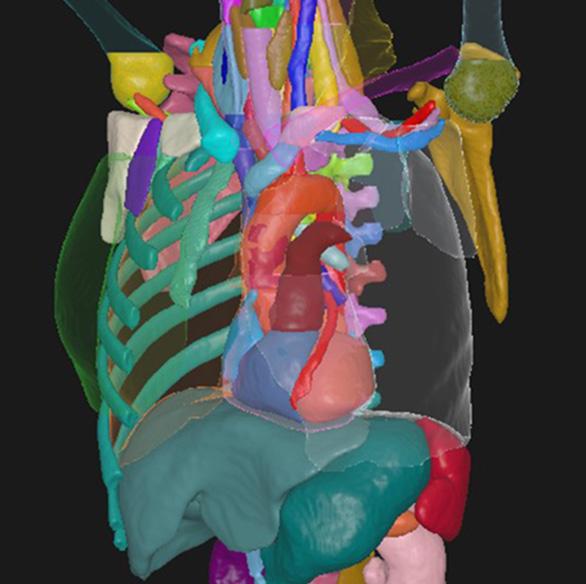

Deep learning capabilities in RayStation®* help make image segmentation quicker and more consistent. A high-speed GPUpowered algorithm is capable of producing consistent segmentation results using guideline-based segmentation models that have been trained and evaluated on curated data for different body sites.

THORAX/ABDOMEN CT

STRUCTURES

HEART SUBSTRUCTURES

A_Aorta_Asc_Prox NEW

A_Aorta_Root NEW

A_LAD

A_Pulmonary NEW

Atrium_L NEW

Atrium_R NEW

V_Pulmonary NEW

V_Venacava_S_Prox NEW

Ventricle_L NEW

Ventricle_R NEW

VESSELS CT

A_Aorta_Arc A_Subclavian_R

A_Aorta_Asc V_Brachioceph_L

A_Aorta_Desc V_Brachioceph_R

A_Brachiocephls V_Iliac_Ext_L NEW

A_Carotid_Int_L V_Iliac_Ext_R NEW

A_Carotid_Int_R V_Iliac_Int_L NEW

A_Carotid_L V_Iliac_Int_R NEW

A_Carotid_R V_Iliac_L NEW

A_Iliac_Ext_L NEW V_Iliac_R NEW

A_Iliac_Ext_R NEW V_Jugular_Int_L

A_Iliac_Int_L NEW V_Jugular_Int_R

A_Iliac_Int_R NEW V_Subclavian_L

A_Iliac_L NEW V_Subclavian_R

A_Iliac_R NEW V_Venacava_I IMPROVED

A_Subclavian_L V_Venacava_S

VERTEBRAE CT